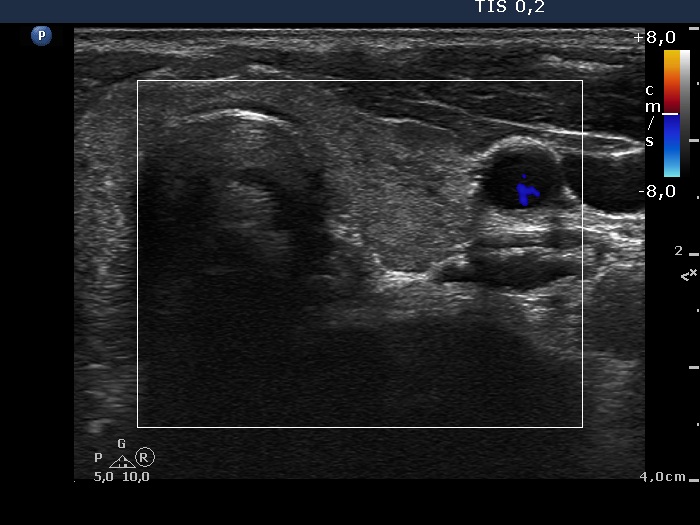

Follow-up investigation 15 months after first visit (ultrasonographic picture 6)

Right lobe, longitudinal scan

Left lobe, transverse scan, color Doppler mode. There is no vascularization on Doppler mode.